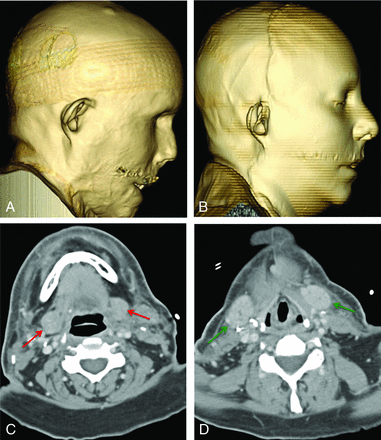

Patient 5 was a female with extensive burn injuries in 2007 after an assault with industrial lye (Fig 5A). Full-face transplantation was performed in February 2013. Two weeks following the surgery, the patient presented with facial swelling (Fig 5B). CT showed soft-tissue edema, lymphadenopathy, but no drainable fluid collection (Fig 5C, -D). Skin biopsy was consistent with grade I/II rejection, which was treated with plasma exchange.

A, Preoperative 3D volume-rendered CT image demonstrates facial deformity due to a severe lye burn. B, Postoperative 3D volume-rendered CT image shows mild facial swelling. C and D, Postoperative axial CT images show edema without a fluid collection. Note the normal-sized recipient submandibular glands (red arrows) and, more caudally, the symmetrically swollen bilateral donor submandibular glands (green arrows), which had been injected with botulinum toxin at the time of transplantation.